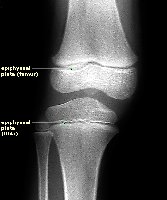

Epiphyseal Plate and Line

The epiphyseal plate is a region of cartilage that allows for bone growth in length. As maturity is reached, it becomes the epiphyseal line.

Epiphyseal Plate: Site of longitudinal growth in children and adolescents.

Epiphyseal Line: Remnant of plate in adults, indicating cessation of growth.